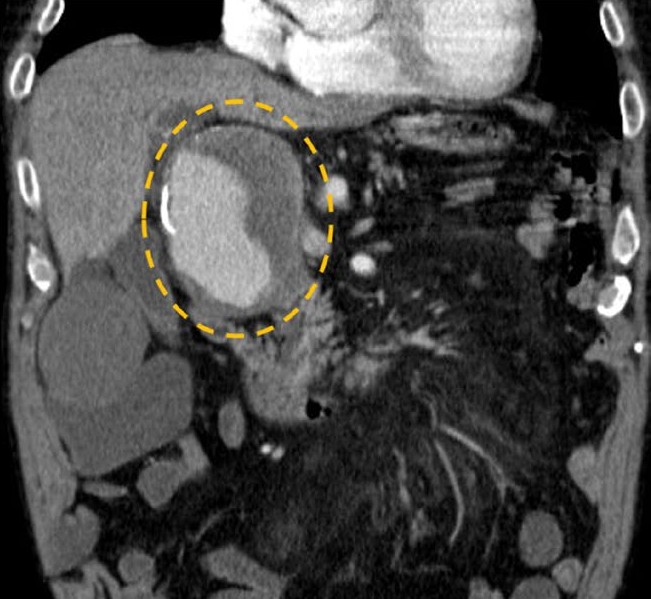

• Exuberant Intra-Abdominal Abscesses Secondary to Streptococcus Anginosus: A Diagnostic and Therapeutic Challenge

José Santos, Jorge Leitão, Arsénio Santos, Lèlita Santos

95-100

DOI: https://doi.org/10.60591/crspmi.390